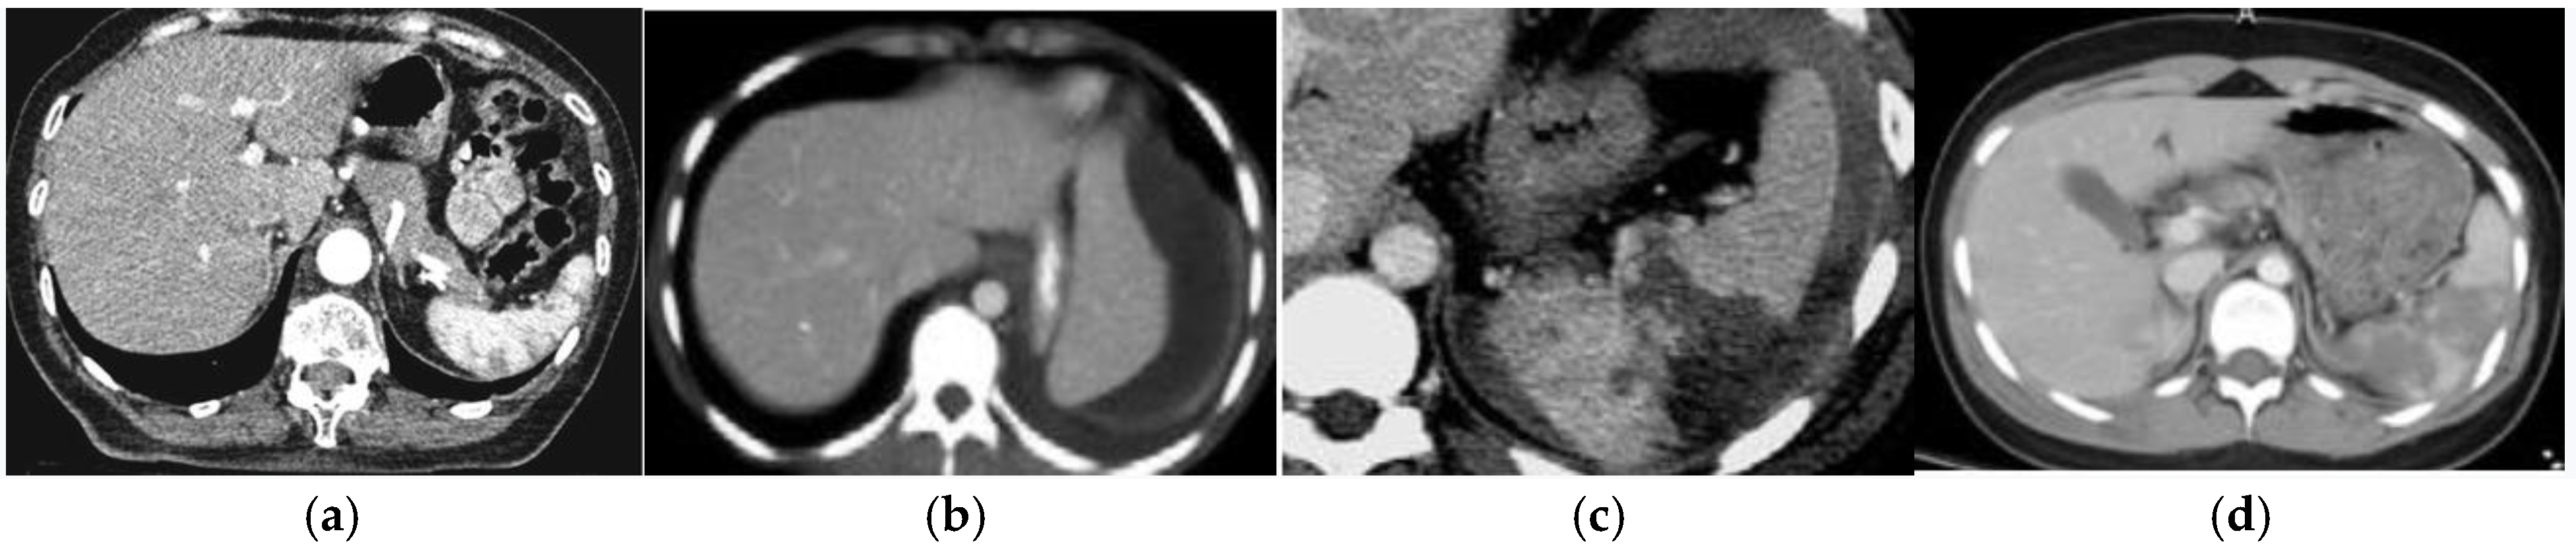

The severity of the injury was determined according to the AAST classification: 7 patients had grade I injuries (9.21%), 21 had grade II injuries (27.63%), 33 had grade III injuries (43.42%), and 15 patients had grade IV injuries (19.73%). Figure 1 shows the differences in ultrasound findings depending on the AAST classification.

Figure 1. (a) Grade I spleen injury, small lacerations as a result of sport injury; (b) grade II splenic injury (hematoma) developed after fall from a standing height; (c) grade III injury as a consequence of a car accident (splenic lacerations); (d) grade IV splenic injury, result of fall from a bicycle.